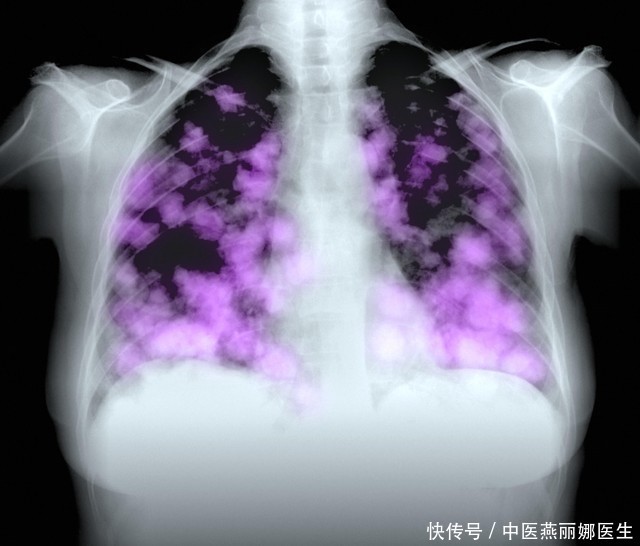

肺癌,这一沉重的医学术语,其本身的分量就足以令人心生惶恐与不安。在中国,肺癌的发病率与死亡率久居高位,它像是一个隐形的恶魔,悄无声息地侵蚀着无数民众的健康与生命。然而,有趣的是,当我们深入了解肺癌的成因时,会发现抽烟并不是唯一的“元凶”。

张先生是一位勤勤恳恳的农民,一辈子都在田间地头劳作,从未抽过一根烟。在一次例行体检中,他竟意外地被诊断出罹患肺癌,这无疑给他平静的生活投下了一颗重磅炸弹。张先生感到难以置信,他不明白自己怎么会得上这种病。医生告诉他,肺癌的成因复杂多样,除了抽烟,还可能与生存环境、生活习惯、遗传因素等有关。

不抽烟的人为何也会得肺癌呢?这其中的缘由错综复杂,如同千丝万缕交织的网,难以一一道明。首先,我们要明白一个事实:肺癌并非只由抽烟引起,它是一个多因素、多阶段的复杂过程。抽烟固然是肺癌的高风险因素之一,它绝非唯一诱因,多种复杂因素交织在一起,共同影响着肺癌的发生。其次,每个人的身体状况和遗传因素都有所不同,这也决定了不同的人对肺癌的易感性不同。有些人即便未曾触碰烟草,但由于其他多种潜在因素的交织影响,他们同样面临着罹患肺癌的风险。

这里,我们不得不提到医学领域的权威观点。世界卫生组织的数据揭示了一个深刻的现实:尽管抽烟被公认为是肺癌的主要诱因之一,然而并非所有肺癌患者都有抽烟史,这暗示着肺癌的成因远比我们想象的要复杂。事实上,越来越多的研究表明,不抽烟的人也有可能因为其他因素而患上肺癌。这一观点已经得到了国内外众多权威专家的广泛认可,进一步证实了其科学性和可信度。